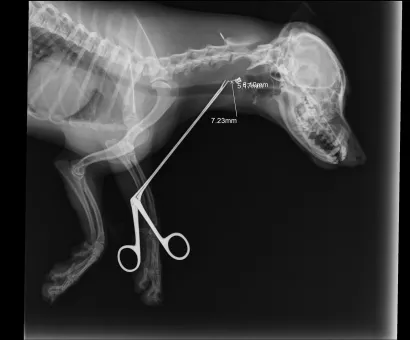

Maleni pas mješanac pogođen je dijabolom u vrat, a budući da je metak ostao smješten na nezgodnom mjestu blizu kralježnice, veterinar Mate Karaula iz Daruvara koji liječi Lenu, odustao je od vađenja metka zbog daljnjeg rizika po kujicu.

Prema nalazu veterinara dr. Mate Karaule, rendgenska snimka pokazala je da se metak, točnije dijabola, nalazi u području između atlasa i aksisa – dijela vratne kralježnice.

- Veličina projektila procijenjena je na 6,10 do 5,16 milimetara, a zbog dubine položaja i blizine kralježnice procijenjeno je da bi pokušaj vađenja mogao izazvati ozbiljne komplikacije. Zbog toga se odustalo od kirurškog vađenja metka.

Pas je primio injekcijsku sedaciju, obavljene su dvije rendgenske snimke i kirurška obrada rane, kazao nam je dr. Karaula.